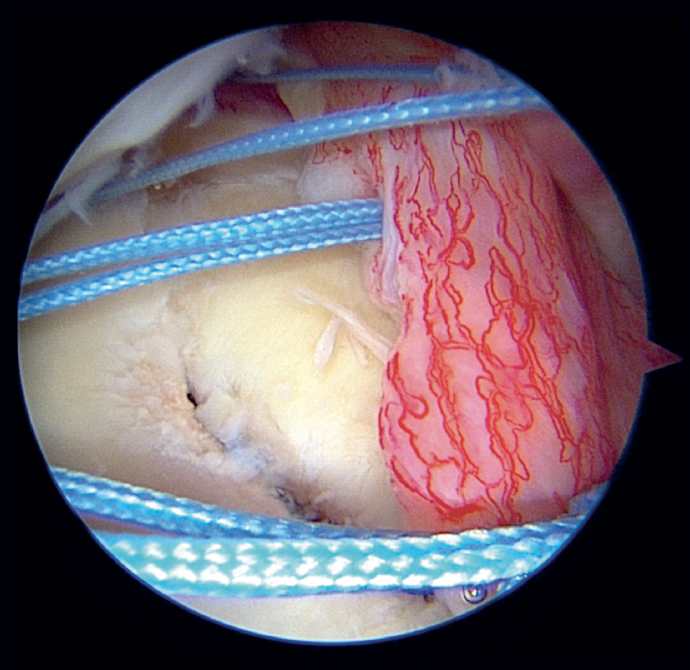

In the classical Porcellini-Sugaya technique, debridement and roughening of the bone margins of the fracture was carried out with synoviotome, rasps and curettes (Figure 2). All-suture anchorings were used for the repair. The first anchoring was placed in the lowermost zone of the defect (Figure 3), and one its extremities extended to the damaged labrum in the lowermost zone, followed by knotting. The second anchoring was placed in the uppermost zone of the defect (Figure 4), in the same way as the first, followed by knotting. In those cases where considered necessary, one or two more anchorings were added proximal to the previous ones. Reduction and stability of the fragment was checked.